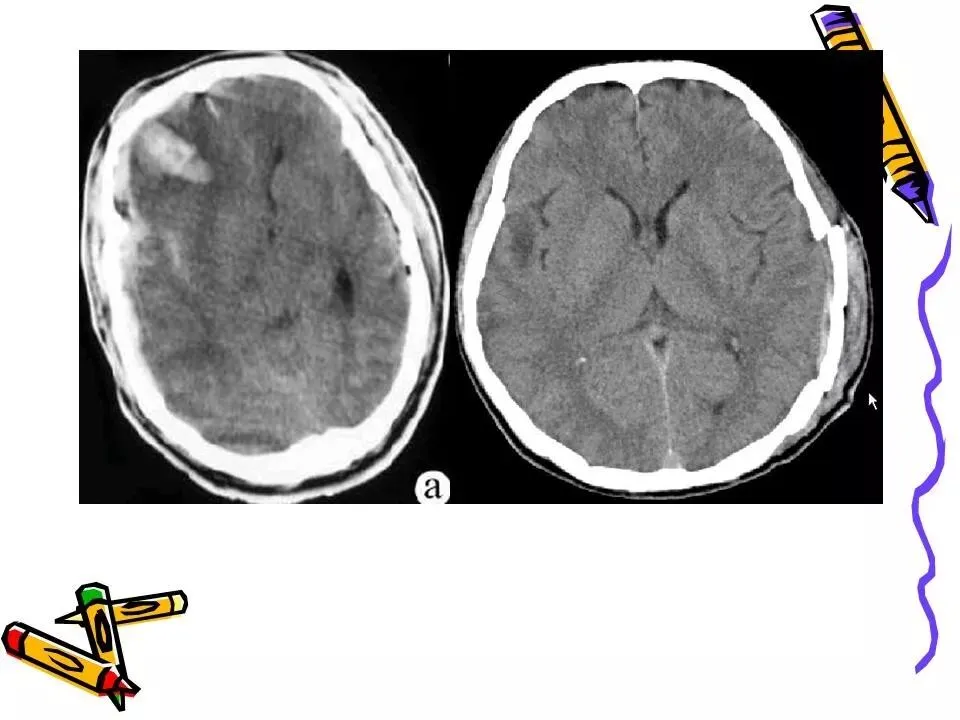

>常见颅脑外伤CT诊断(PPT)

常见颅脑外伤CT诊断(PPT)